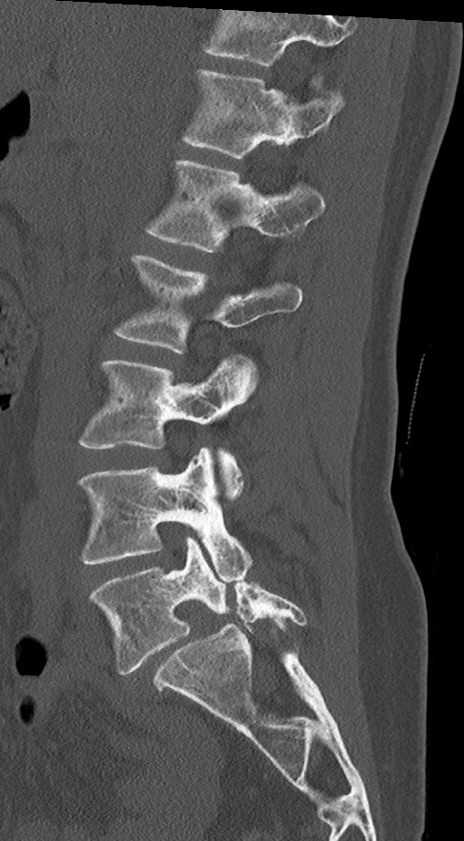

【整形】TIPS症例4 腰椎CT(矢状断像)

腰椎CT